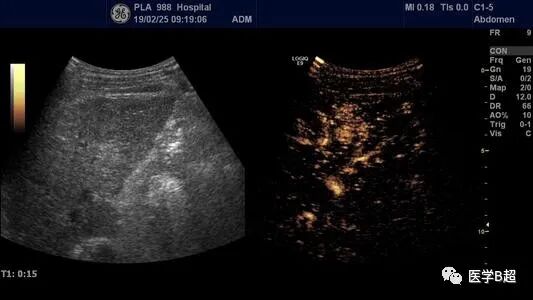

早期微小肝癌在 1-2cm

慢性肝病要求三个月查一次超声,目的一是了解肝质地情况,更重要的是监测早期肝癌的出现,早期微小肝癌在 1-2cm 就已被能发现,对早期治疗意义重大,如在检查中发现了异常结节,经超声造影甚至活检,可以很快确定是否是肝癌,早期微小肝癌不管是手术还是介入,疗效都相当不错,存活 5 年、8 年已是很常见,甚至可完全治愈。